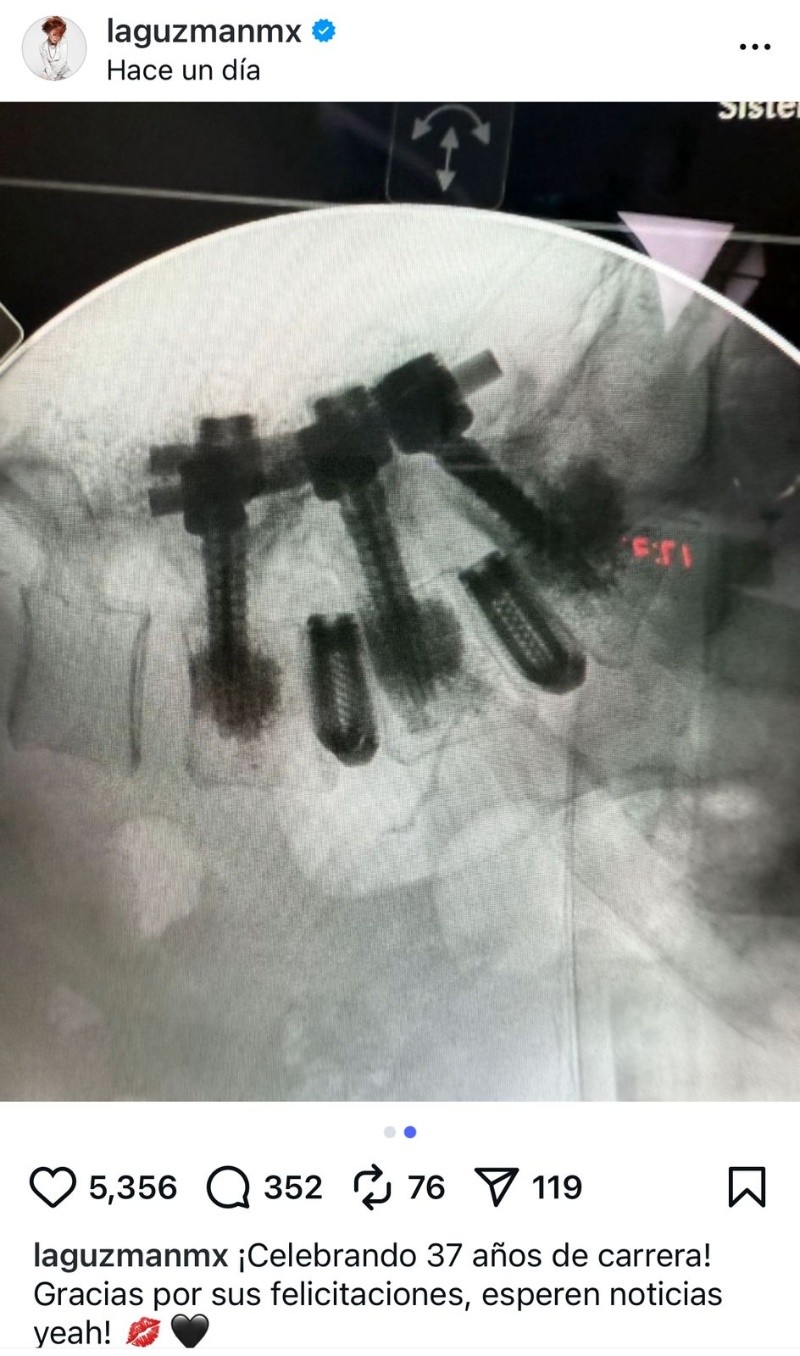

Alejandra Guzmán celebra sus 37 años de carrera con una operación de columna exitosa. La cantante reapareció en sus redes, e informó que con esta intervención pone punto final a un padecer que empezó hace 13 años; la cantante se sometió a una cirugía de columna vertebral y se recupera satisfactoriamente.

A través de un audio que adjuntó a una reveladora imagen, la Guzmán compartió con sus seguidores cómo se encuentra y qué es lo que viene para ella en el futuro.

En su publicación, se ven varios tornillos grandes atravesando múltiples vértebras. Estos tornillos se usan para inmovilizar segmentos de la columna.

En la imagen, se observa una barra metálica que conecta y estabiliza las vértebras donde se colocaron los tornillos. Algunas partes del implante hacen un ángulo, lo que puede indicar corrección de deformidades o estabilización de fracturas complejas. Este tipo de cirugía se realiza en afecciones severas de la columna como fracturas, escoliosis grave, inestabilidad vertebral, o para tratar ciertos tipos de enfermedades degenerativas o tumores.

El objetivo es proporcionar la máxima estabilidad, facilitar la recuperación o evitar daño neurológico adicional. Por la complejidad del implante, parece una cirugía de columna de alta especialización, probablemente en la zona lumbar o torácica (parte baja o media de la espalda).